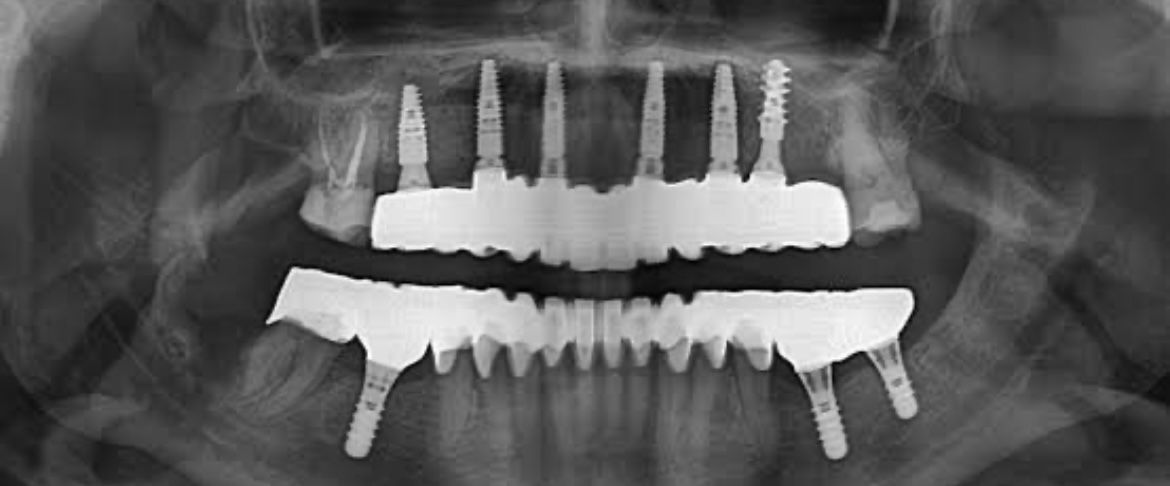

Radiologie dentaire

Examens radiographiques RVG et panoramiques pour un diagnostic précis.